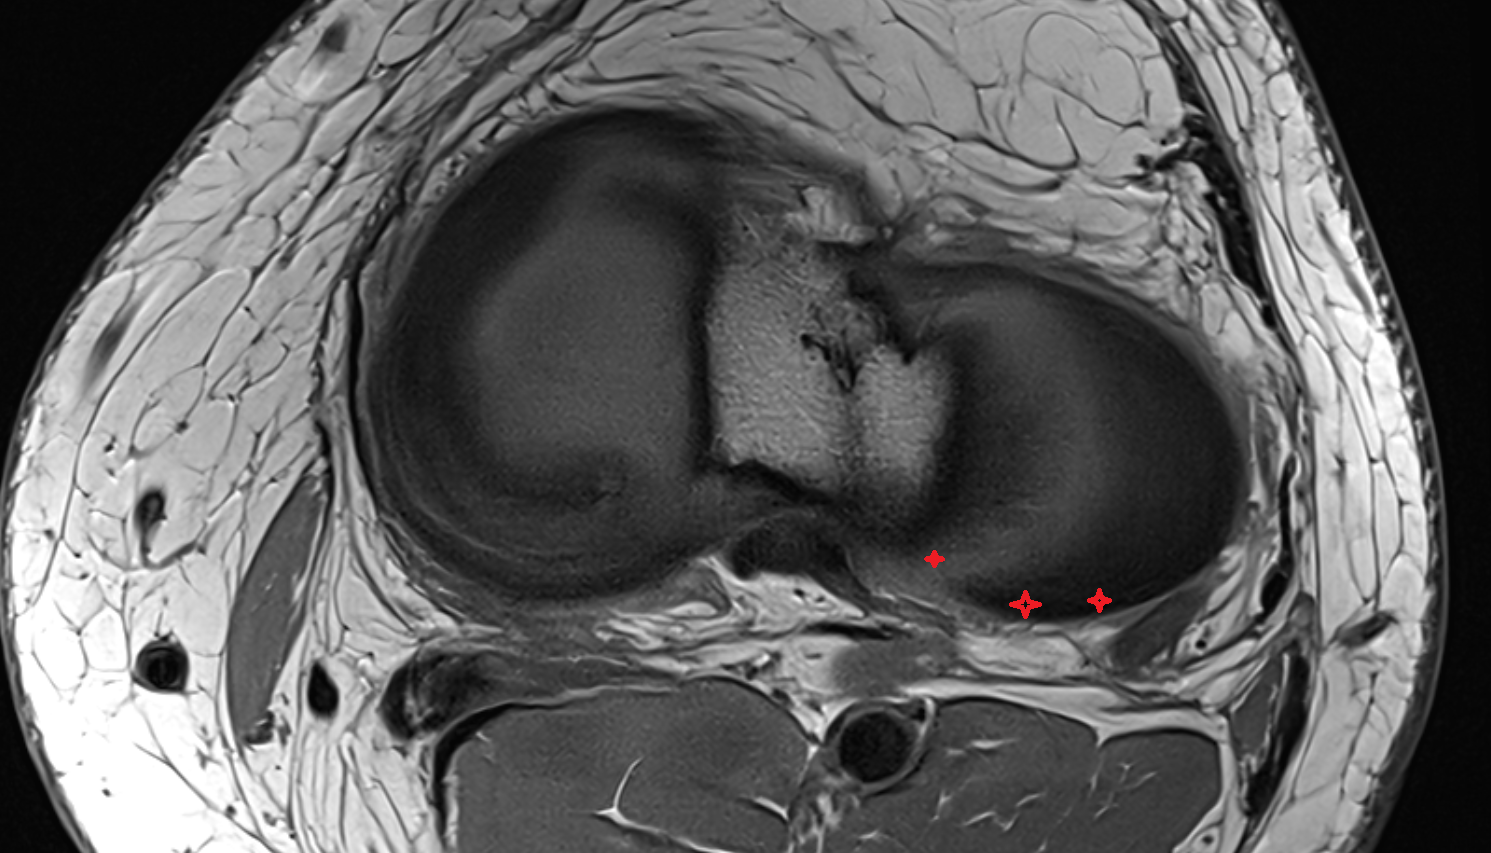

- Anterior cruciate ligament

- Posterior cruciate ligament

- Medial meniscus

- Lateral meniscus

- Anterior horn of lateral meniscus

- Posterior horn of lateral meniscus

- Knee Joint